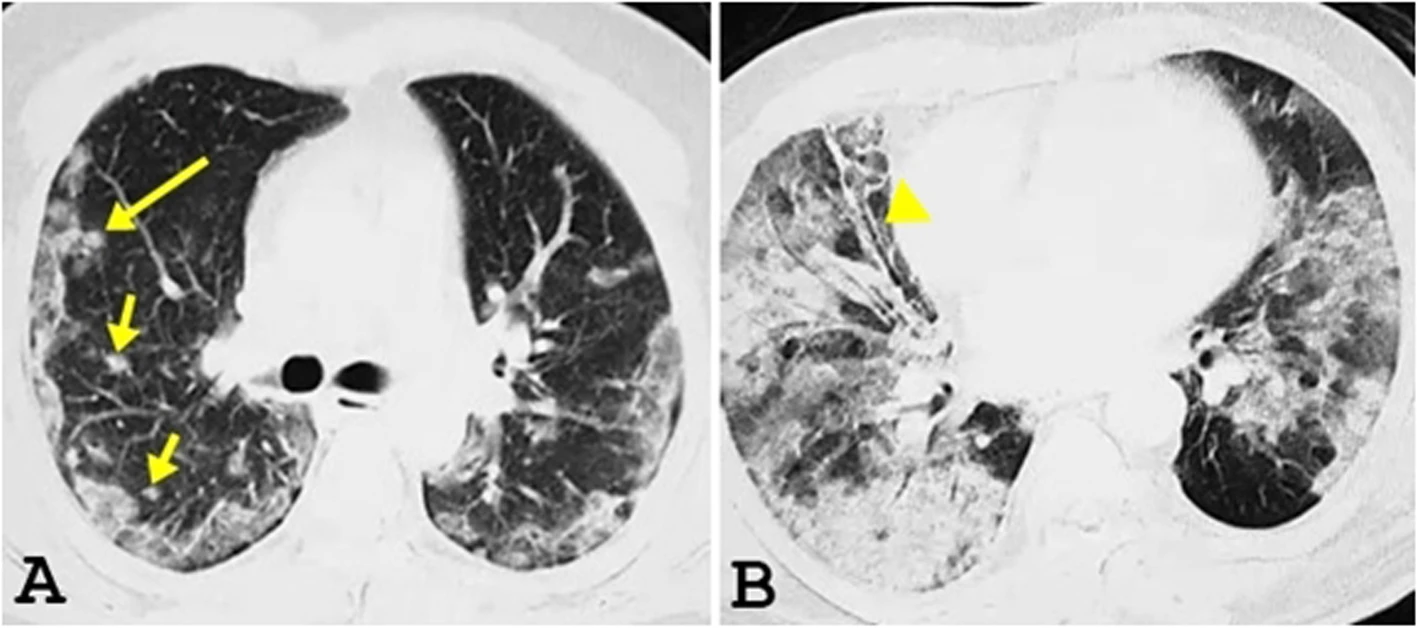

COVID-19 CT Scans

37 yrs

52 yrs

73 yrs

ground-glass opacity (GGO)